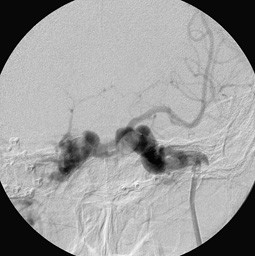

Carotis sinus cavernosus fistel. Ihren Ästen und Sinus cavernosus. Direkte Shuntverbindung zwischen der Arteria carotis interna und des Sinus cavernosus. A Angiographie der Arteria carotis communis in seitlichem Strahlengang.

Anhand der Barrow Klassifikation werden Carotis-Cavernosus Fisteln in 4 Gruppen eingeteilt. Das Coiling bezeichnet ein neurochirurgisches angiographisch gestütztes Verfahren zur endovaskulären Embolisation zerebraler Aneurysmen und arteriovenöser Fisteln Carotis-Sinus-cavernosus-Fistel. Mehr zu Symptomen Diagnose Behandlung Komplikationen Ursachen und Prognose lesen.

Eine spezielle Komplikation nach einem Schädel-Hirn-Trauma insbesondere nach Schädelbasisverletzung stellt die Carotis-sinus-cavernosus-Fistel dar. Carotis mit vollständiger Rückbildung der Symptome in einem Fall. Typisch sind gestaute episklerale Venen bei wechselnd ausgeprägter Protrusio bulbi.

Carotis interna im Sinus cavernosus verletzt fließt das Blut der Arterie in den venösen Sinus. Traumatisch frontobasale Schädelbasisfraktur Aneurysmaruptur A.